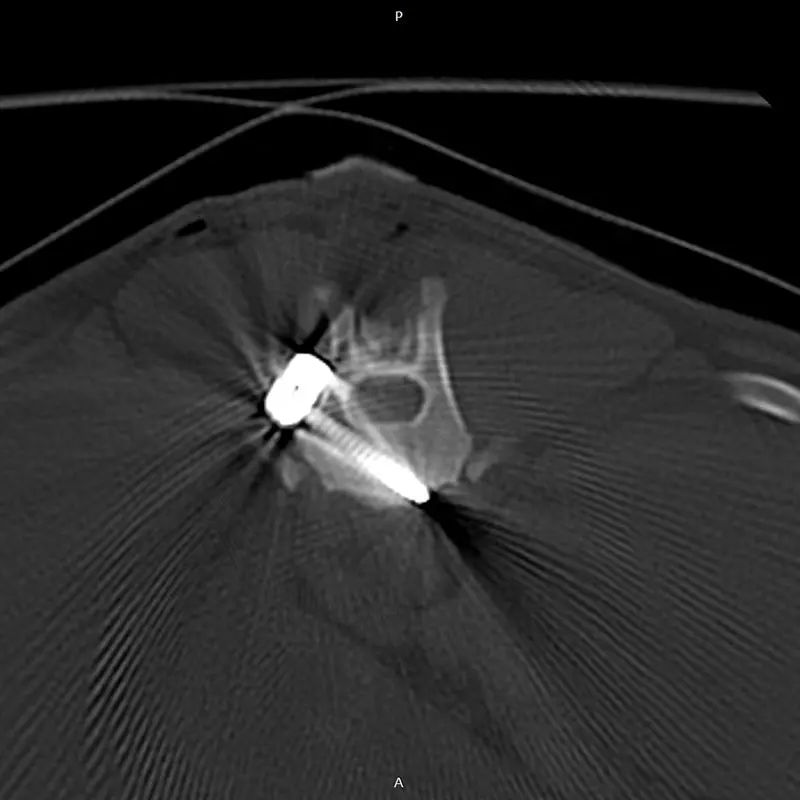

We have been using the system for years, and clinical experience greatly supports its reliability, even in difficult, challenging situations. It is excellent for stabilizing the spine, especially in the thoraco-lumbar region. If the connecting rod is placed ventrally from the articular processes, the screws are placed in the vertebral body at a 45-degree angle at the base of the transverse processes, so that they grip the largest possible bone material. (see CT images). Up to 2 clamps can be attached to a vertebral body from one side. Compared to other, more complex, multi-piece spinal stabilization systems, it is thinner and fits better on the surface of the bone. The screw axis is located ont he side of the axis of the connecting rod (the rod and the screw are not located on top of each other), the clamps can be rotated and slid, so that the largest possible bone stock can be freely accessed during surgery.

In our case, we stabilized the T13-L1 vertebral luxation of a 4-year-old dachshund, where the ligament system of the vertebral body was damaged during a car accident.